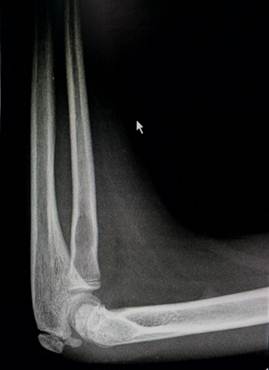

Снимок локтевого сустава ребенка в возрасте 1 года. Заметно ядро

окостенения головчатого возвышения и латерального вала блока плечевой кости.

Ребенок в возрасте 2 лет. Ядро окостенения головчатого возвышения

увеличилось и стало шире. На метафизарной зоне можно увидеть небольшую плоскую

площадку – зону медиального надмыщелка.

Возраст 3 года. Появилось адро окостенения головки лучевой кости.

Площадка медиального надмыщелка отчетливо контурируется.

4 года – 6 лет

Завершение оссификации хряща метафизарной зоны плечевой кости и

контурирование зоны нахождения медиального надмыщелка. В 6 лет появляется ядро

окостенения медиального надмыщелка. Костная ткань начинает заполнять локтевой

отростк и его тень накладывается на тень метафиза плечевой кости на прямых

снимках. Головка лучевой кости имеет сформированную зону роста.

Возраст 6 лет. Появилось ядроокостенения медиального надмыщелка.

Хорошо прослеживаются основания венечного и локтевого отростков. На прямом

снимке тень локтевой кости находится

выше уровня суставной щели.

7 лет – 10 лет

В этом возрасте начинается процесс окостенения медиального вала

блока, в котором появляются мелкие, неправильной формы ядра окостенения. В 8

лет появляется ядро окостенения вершины локтевого отростка. Чуть позже к нему

добавляются мелкие ядра - спутники. К концу периода появляется ядро окостенения

латерального надмыщелка.

Возраст 7 лет. Ядро окостенения головчатого возвышения плавно

распространяется в латеральный вал блока и он начинает прослеживаться. Рядом с

ним заметно маленькое линейное ядро окостенения в медиальном вале блока. Появилось два маленьких ядра окостенения

вершины локтевого отростка.